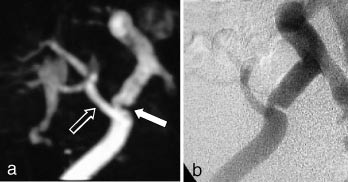

Perifere kar

En av de vanligste indikasjonene for kateterangiografi er arteriosklerotisk sykdom i underekstremitetsarteriene. Stenoser vil kunne behandles i samme seanse med perkutan transluminal angioplastikk (PTA). MRA gir ikke mulighet for behandling, men metoden har et stort diagnostisk potensial. Hittil har man mest benyttet 2D-innstrømnings-MRA for fremstilling av arteriene i underekstremitetene. Metoden er tidkrevende (ca. 40 minutter for å dekke området fra distale aorta til ankler med tynne tverrsnitt) og gir ofte overestimering av stenosegrad og lengden av okklusjoner. Metoden er et særlig godt supplement når kateterangiografi er umulig eller inadekvat pga. utbredte karokklusjoner. 2D-innstrømnings-MRA er svært sensitiv for langsom blodstrøm, og vil f.eks. kunne påvise åpne perifere arterier ved uttalte proksimale okklusjoner. Den beste MRA-metoden er likevel kontrastforsterket MRA, forutsatt ny og rask MR-apparatur med mulighet for å flytte pasientbordet under bildeopptaket. Denne metoden gjør det mulig å undersøke bekken- og underekstremiteter i løpet av én kontrastbolusinjeksjon, og kvaliteten på disse opptakene er nesten identisk med den som oppnås med kateterangiografi (20). Utviklingen går mot at man velger MRA til den diagnostiske angiografiske utredningen, mens kateterangiografi reserveres de tilfellene der intervensjonsbehandling er aktuelt.